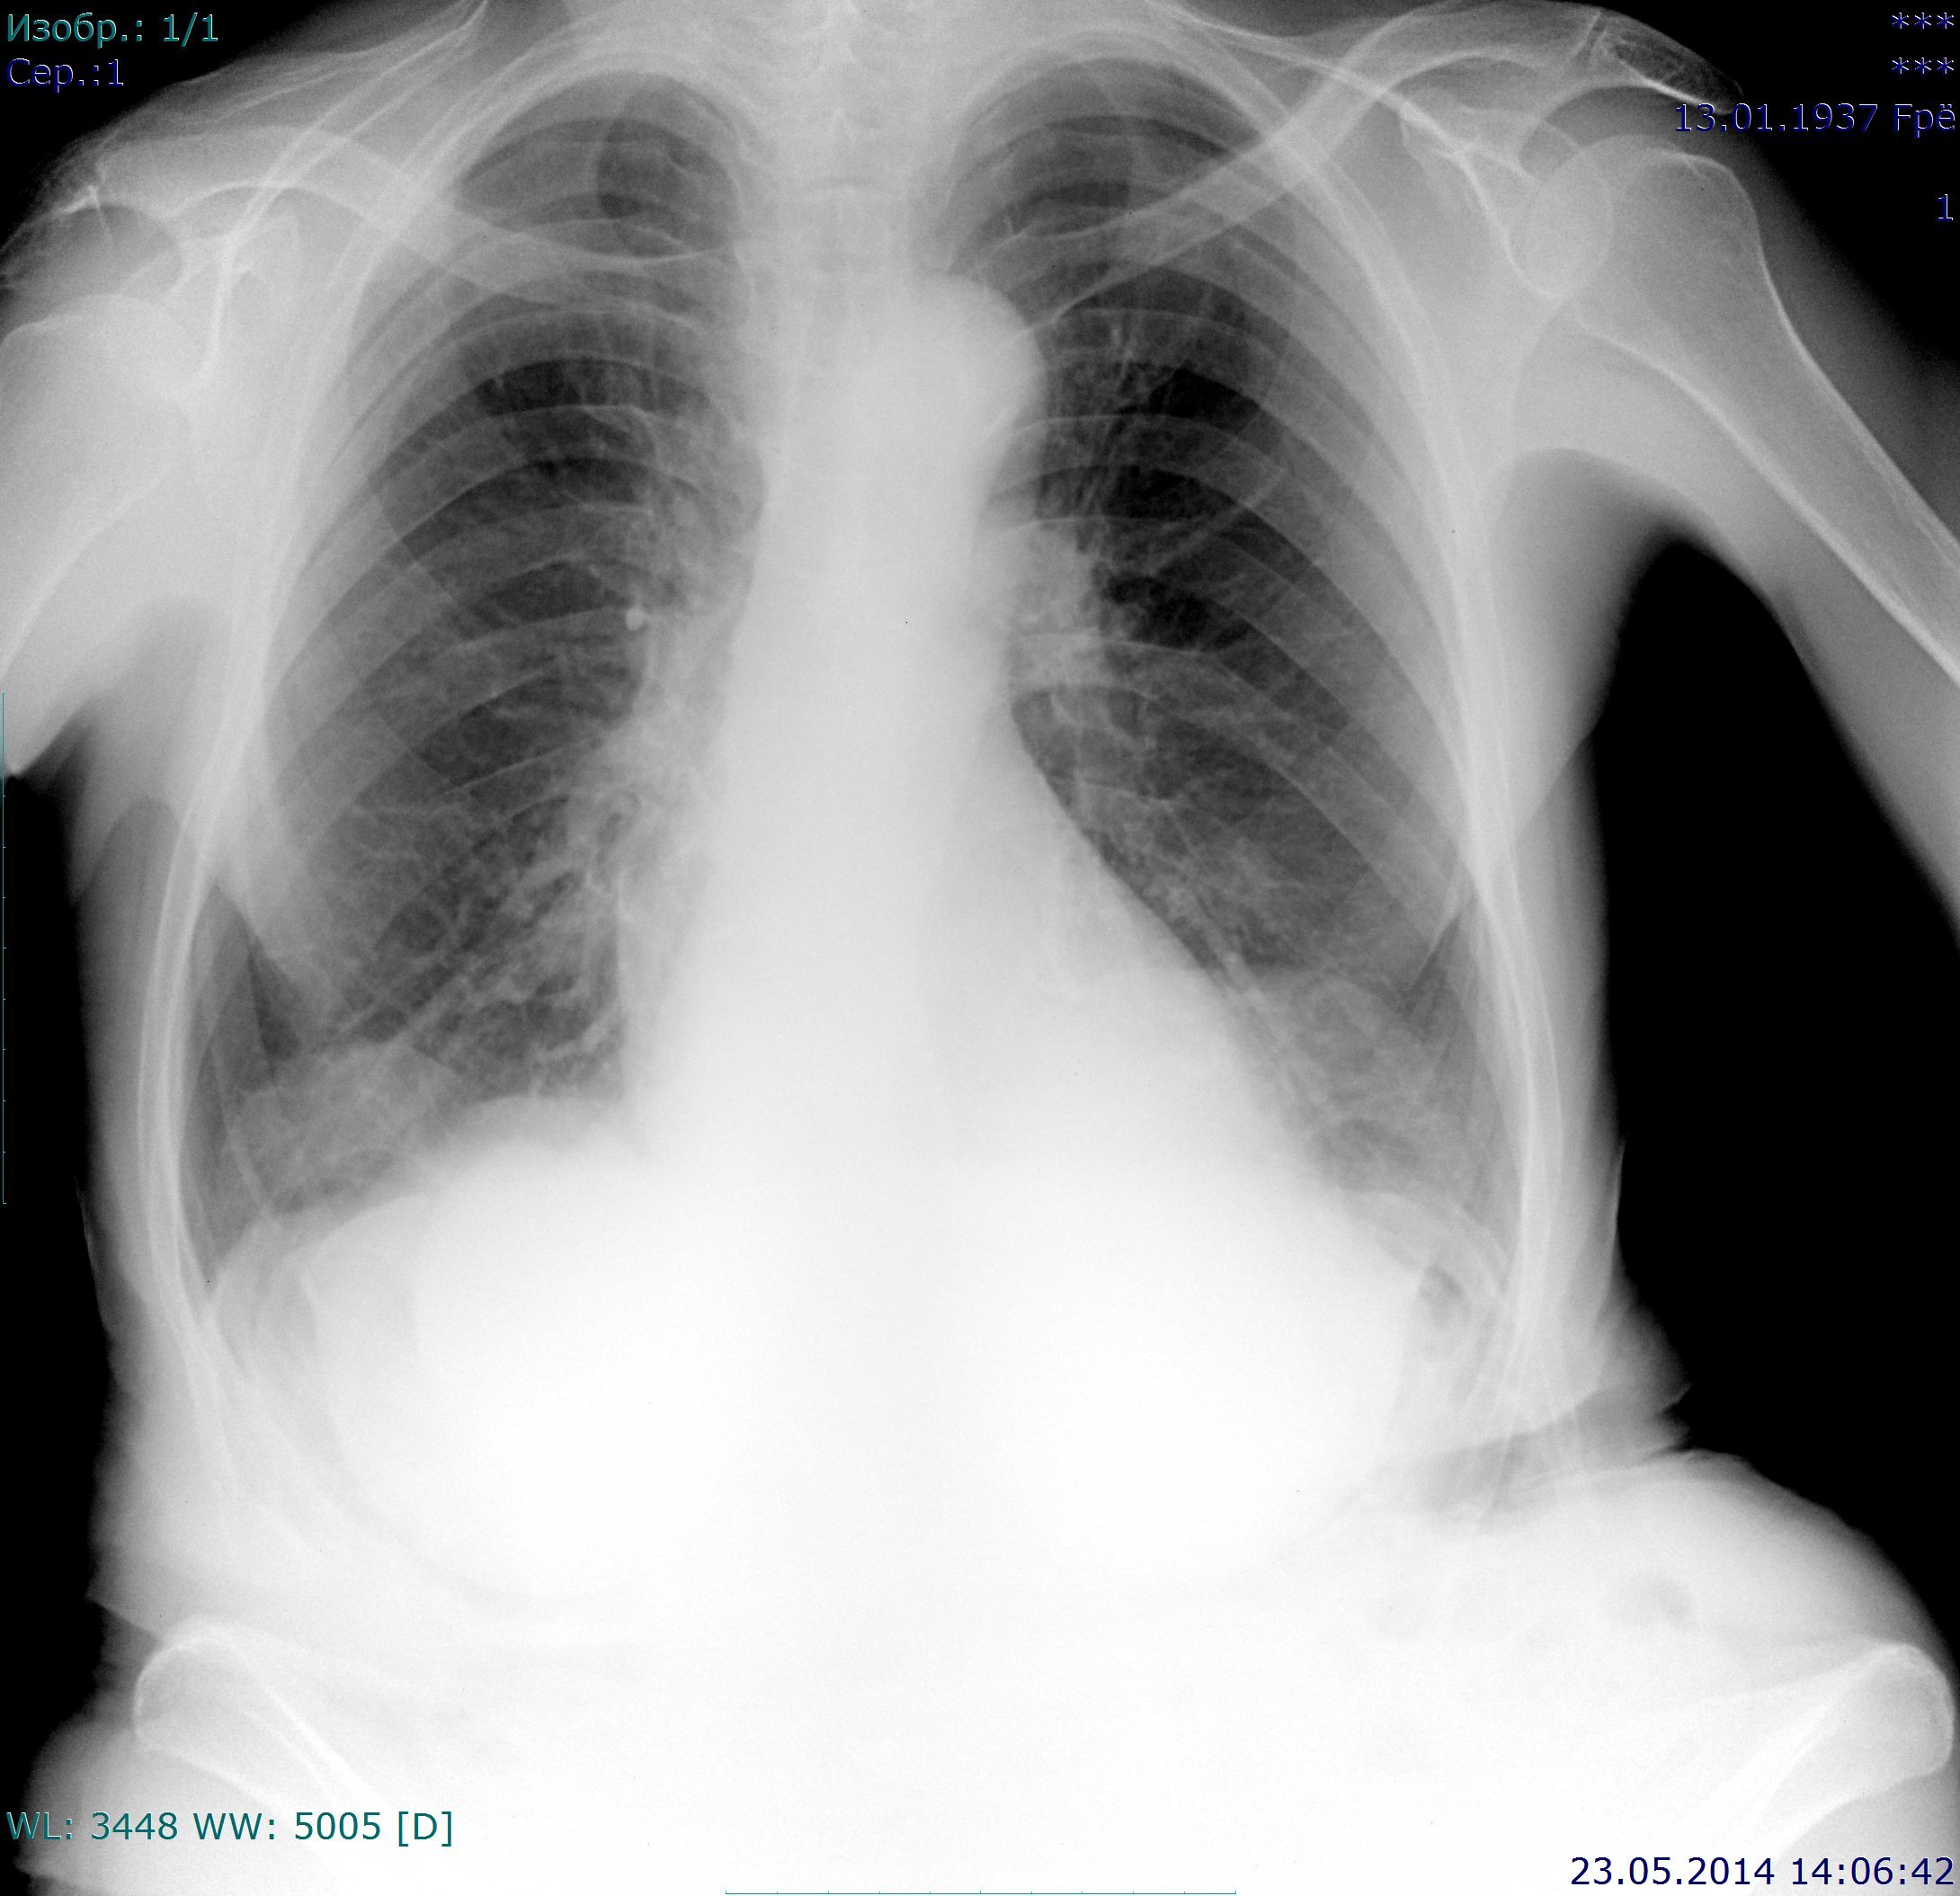

Пациентка 1937 г.р., проф флг. Архива нет. Пневмосклероз.

Тени, отмеченные красным - частичная релаксация куполов диафрагмы (передних её отделов)?

По боковому релаксации не видно. Считаю, что отмеченные Вами тени это задние отделы куполов диафрагмы (снимки выполнены с наклоном)

Грыжи Богдалека скорее.

Напротив, отмеченное - тени передних отделов куполов диафрагмы. Точно не грыжи, которые с Любовью рекомендовались Вам.;)